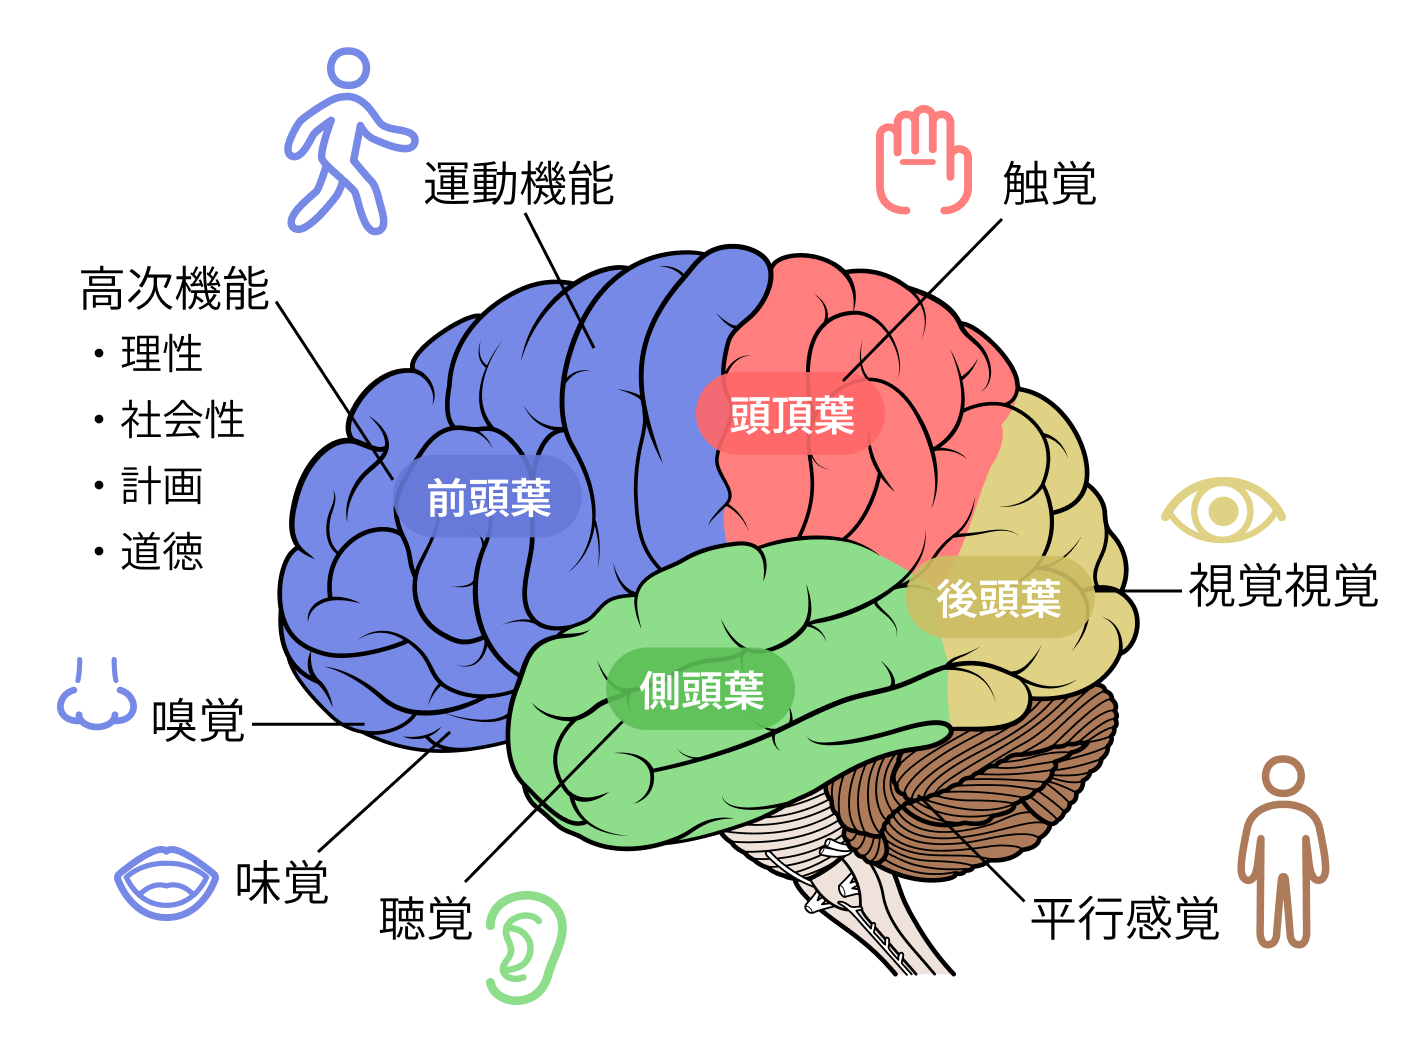

脳の「部分機能改善」を目指す新しいデイサービス。認知症患者は脳がダメージを受けているといっても脳全体が機能低下しているわけではない。ダメージに合わせた「部分」トレーニングをする必要があります。

【症状別・脳の機能区分】

・空気が読めない、落ち着きがない人

→ 前頭前野

・聞いたことを直ぐに忘れる人

→ 海馬

・会話の内容が理解できない、文字が読めない

→ 左側頭葉

・物品の認知、理解ができない人

→ 右側頭葉

・自身の火傷や怪我に気付けない人

→ 頭頂葉

・徘徊する、迷子になる人

→ 後頭葉

上記のように特定部位を鍛えるなど、具体的な症状に対応したトレーニングを提供します。